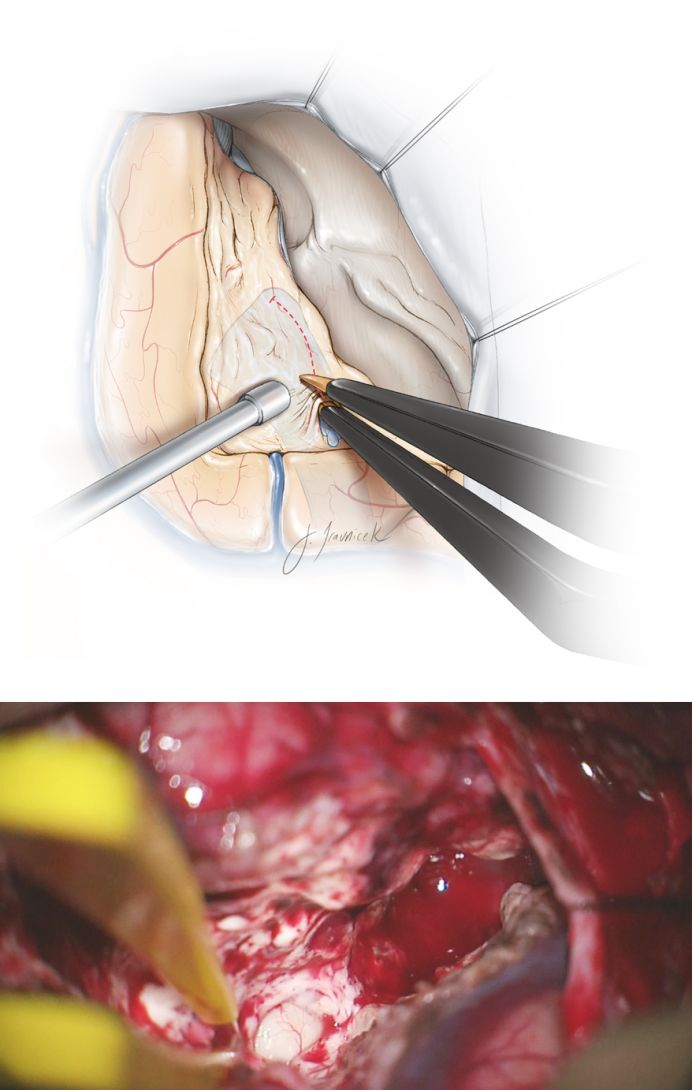

图13. 切断脑室外侧壁的枕颞神经纤维束,可扩大暴露海马。平行于海马外侧缘切开。此外,沿枕颞纤维束切开梭状回,直到发现枕颞回内侧的蛛网膜。吸引装置前端(下方术中照片)即脉络丛。

Meyer’s袢沿颞角顶部和外侧面走行。术者可通过保持梭状回内侧平面以内操作以避免颞上象限盲。

图17. 杏仁核的下三分之二和整个钩回(位于海马旁回前部)分别用白色和绿色突显,切除这些中间结构始于软膜下离断。切除杏仁核时应注意前文提到的背外侧平面。

图18. 在杏仁核切除的全过程中维持腹侧平面解剖,同时操作限于覆盖基底池的蛛网膜层。在整个过程中,笔者保持这些蛛网膜层的完整以保护其下的动眼神经、PCA及脑干。通过其相应的蛛网膜膜识别动眼神经和小脑幕游离缘,以确保足够空间向内切除钩回(上图)。向后切除的极限在钩回与海马头连接处(下图)。笔者应用一扁平剥离子剥去钩回余下覆盖于神经上的薄层蛛网膜(术中图片)。

图19. 在切除杏仁核和钩回后进行内侧海马结构的切除,穿过钩束和边缘叶内侧的海马旁回直至整个海马。离断海马内侧部分时注意保留其侧面的脉络丛,避免损伤脉络膜前动脉(ATL手术引起偏瘫的原因之一)。在手术过程中取一小棉片块覆盖海马,应用吸引装置完成切除。